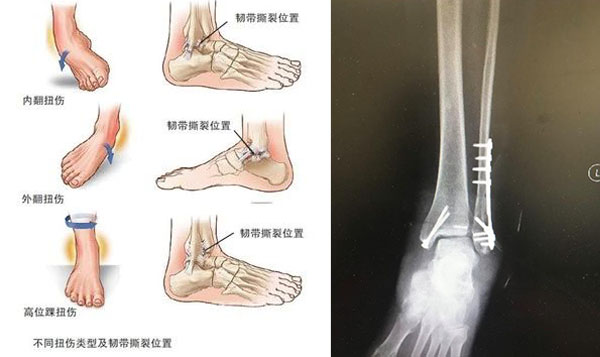

“小崴脚”大隐患!踝关节扭伤怎么办?

一旦出现踝关节扭伤,初期处理好后,如果脚踝依然疼痛或者肿胀明显,建议及时去医院做个检查,看是否存在韧带撕裂或骨折等问题,例如X光片、磁共振等,如损伤严重需要及时进行手术治疗。